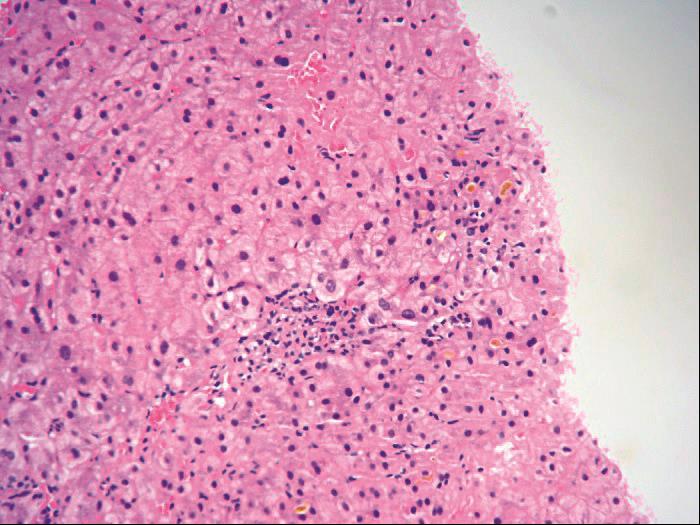

3)界板不整(糜烂):

表现为汇管区周围细胆管增生,沿界板伸向小叶内,同时伴局部HSC活化,导致界板不整,应与淋巴细胞性碎屑坏死相区别。常见于酒精性肝炎及酒精性肝炎肝硬化,发生率分别达79%及99%(图4-3-5)。

图4-3-5 酒精性肝病

肝Kupffer细胞活化,增生(免疫组化CD 68